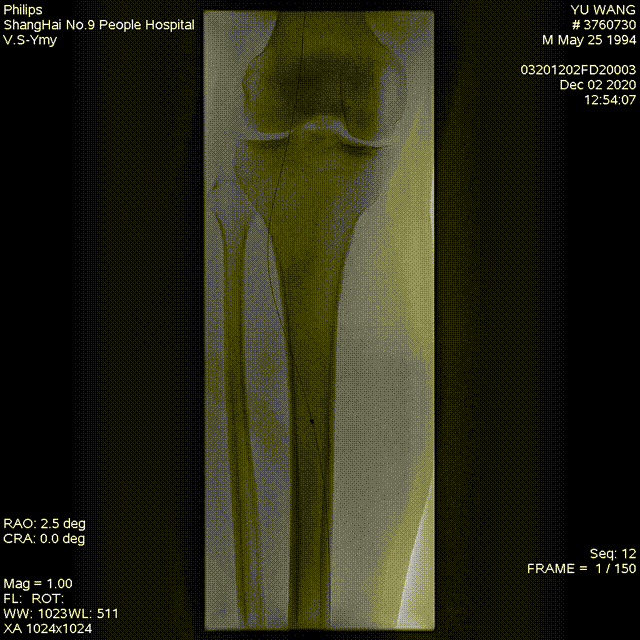

★手术过程

术中顺行穿刺到达狭窄或闭塞病变段附近,在病变段近端予硝酸甘油/罂粟碱扩血管及尿激酶溶栓,导丝通过狭窄或闭塞病变段到达远端流出道后,在膝下动脉使用准分子激光系统(CVX-300 准分子激光系统)减容。采用0.9mm-2.0mmELCA激光导管,以小于 0.5-1 毫米/秒的速度缓慢通过病变段,激光能量30-60mJ/mm2,频率25-80Hz,重复2-3次。在获得管腔后,使用1.5mm-3.0 mm球囊进行球囊扩张。

图:激光辅助血管成形术干预的DSA和IVUS成像。

(A) 基线血管造影; (B) 准分子激光减容; (C) 球囊扩张; (D)术后血管造影